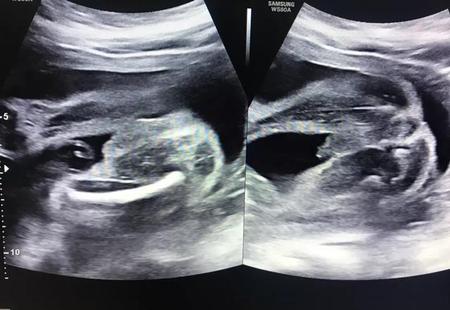

由于男宝宝、女宝宝的泌尿系统不一样,导致在孕检期间胎儿双肾集合系统分离男宝宝的可能性要大一些。所以一般双肾系统分离的胎儿男宝宝的可能性大一些。但是如果遇到自己宝宝双肾集合系统分离,不要忙着猜测宝宝性别,首先要排除胎儿有无合并其他畸形。